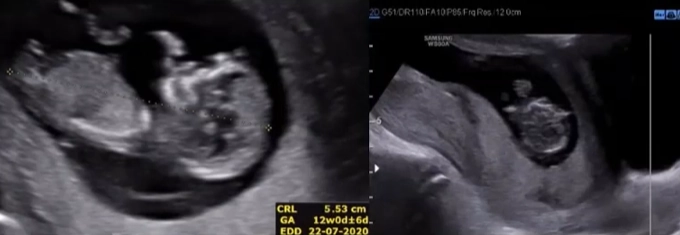

Nhau cuộn mép (Circumvallate Placenta)

16/03/2026